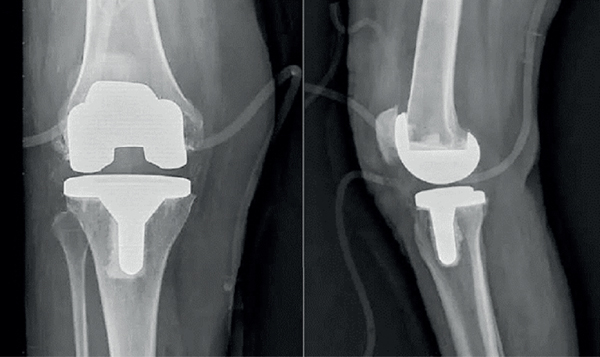

Total knee arthroplasty (TKA) is the most effective surgery for treating moderate to severe knee arthritis [69]. Knee joint prostheses refer to surgical implants used to replace the articular surfaces of the femur and tibia on both sides of the knee. The X-ray films of total knee arthroplasty were as shown in Figure 13.